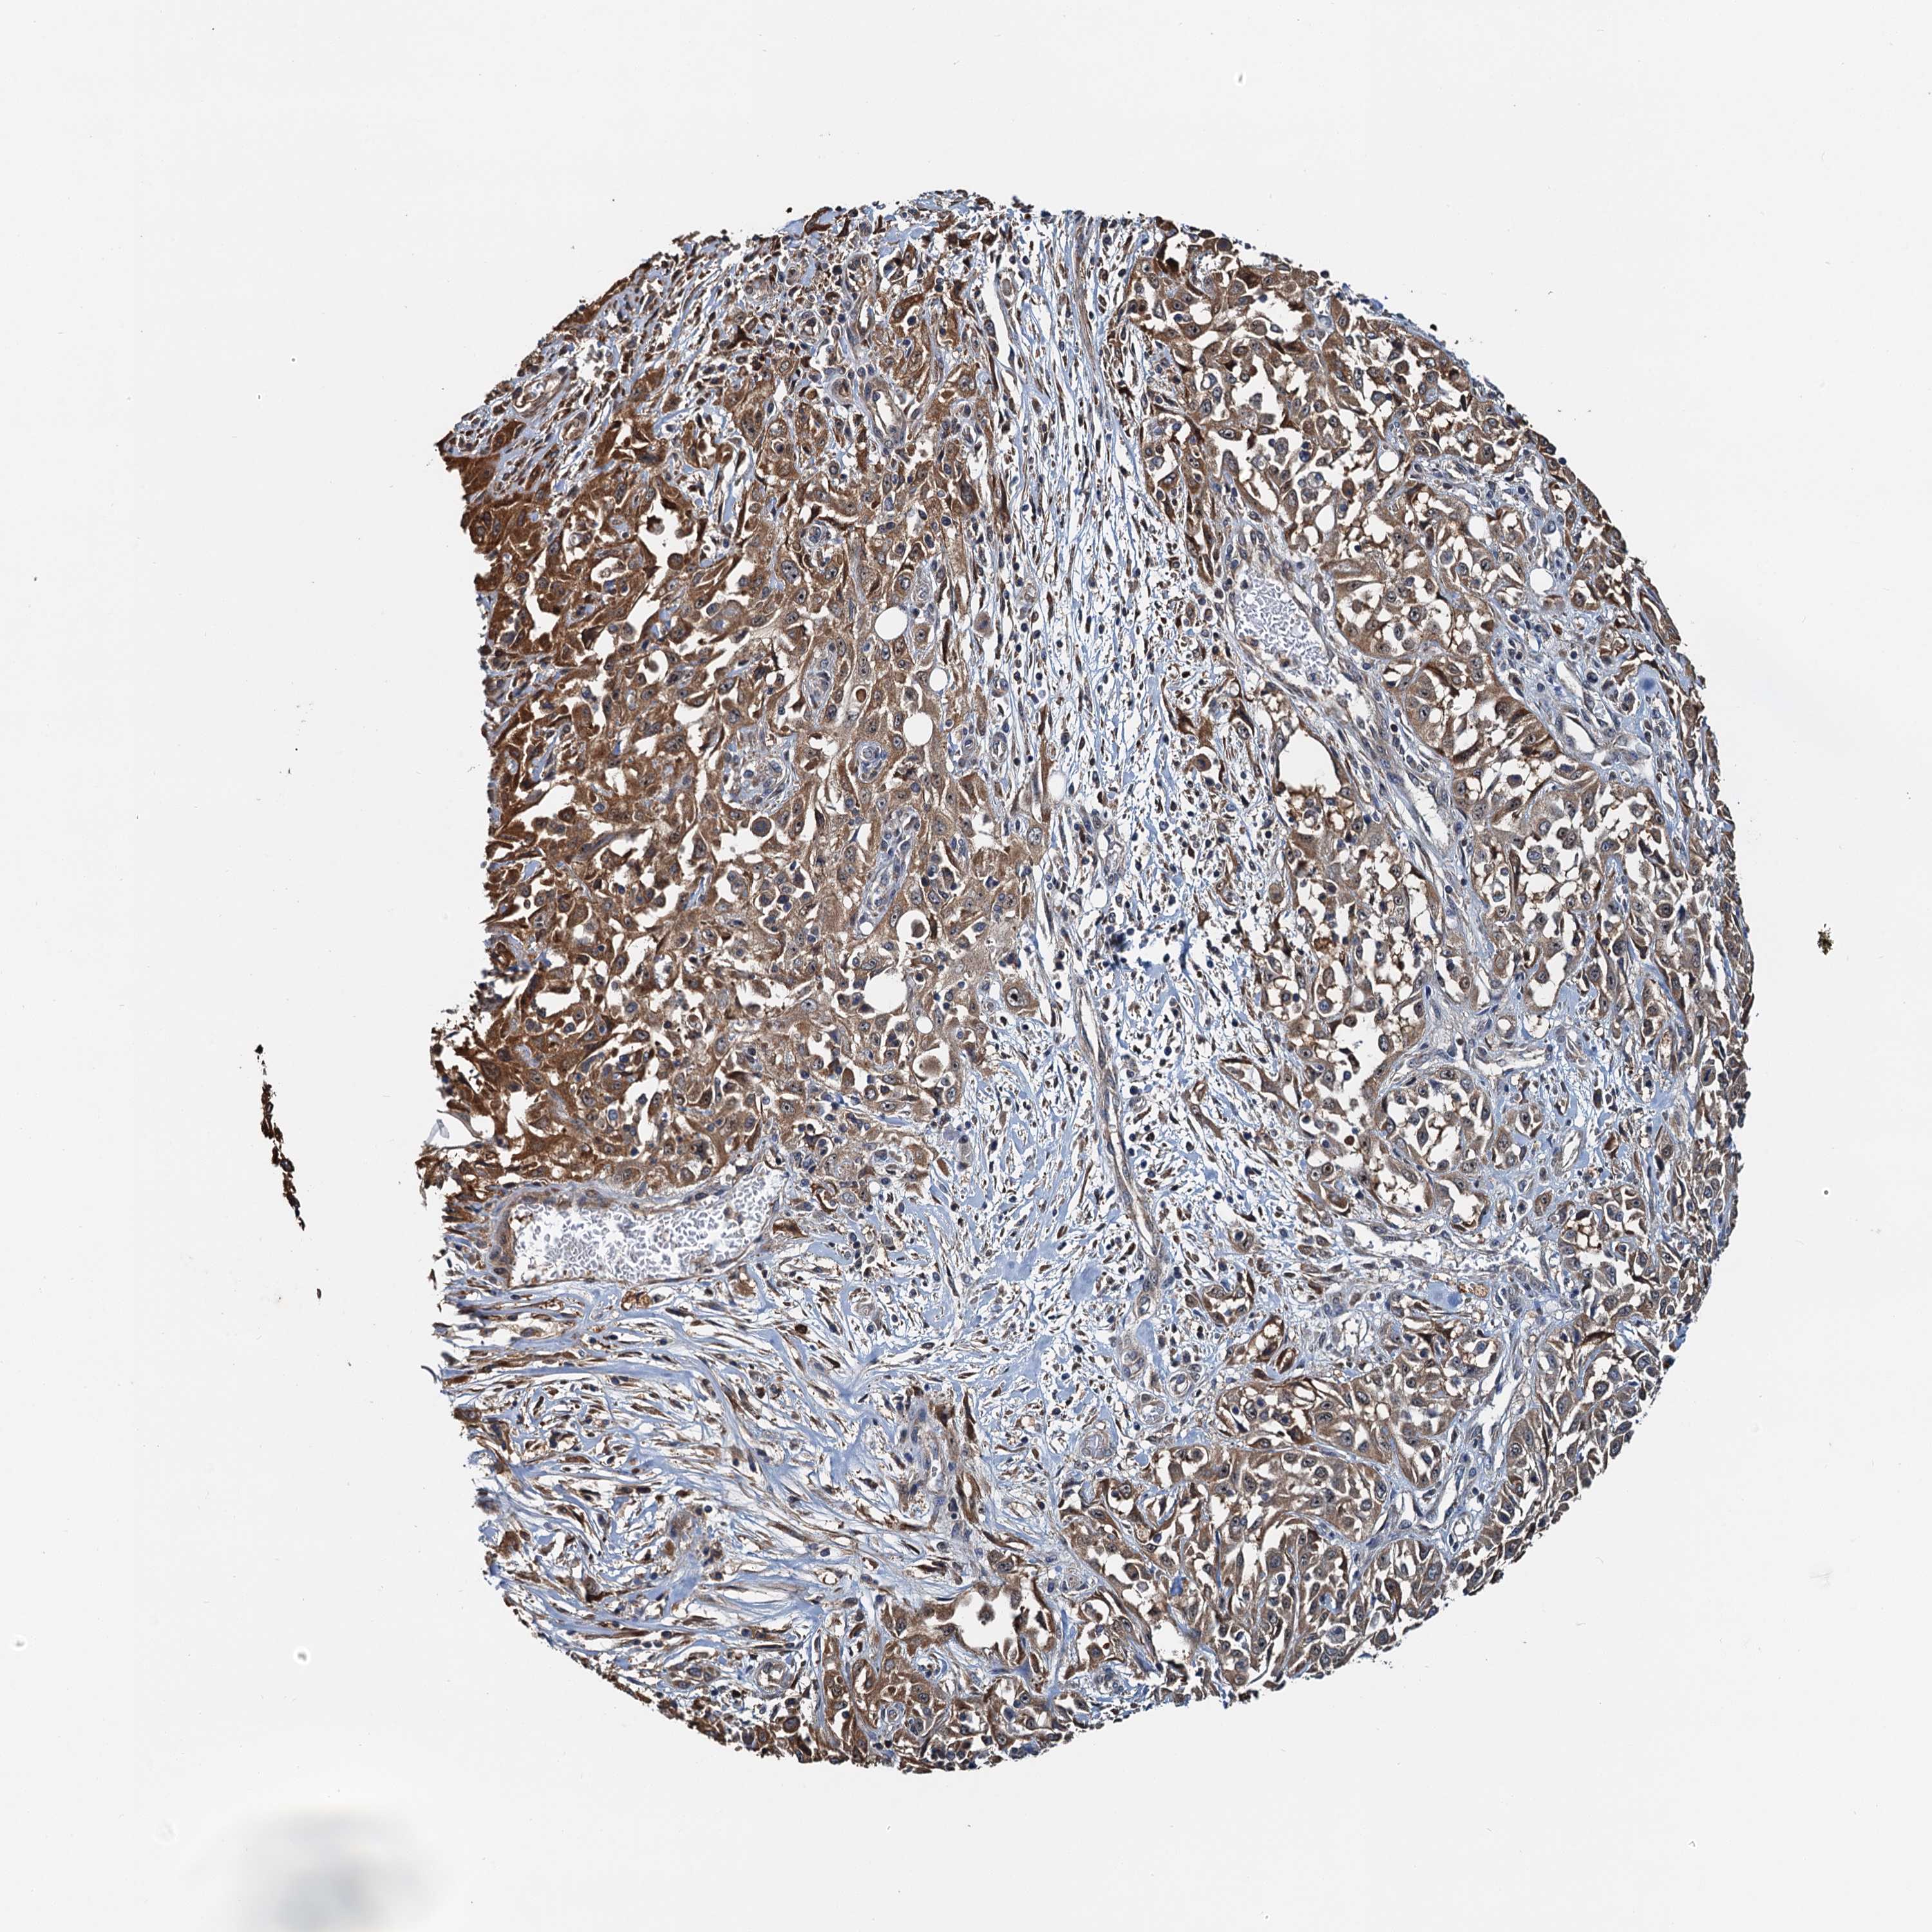

SKIN CANCER - Protein expressioni

A mouse-over function shows sample information and annotation data. Click on an image to view it in a full screen mode. Samples can be filtered based on level of antibody staining by selecting one or several of the following categories: high, medium, low and not detected. The assay and annotation is described here.

Antibody staining in the annotated cell types in the current human tissue is reported as not detected, low, medium, or high, based on conventional immunohistochemistry profiling in selected tissues. This score is based on the combination of the staining intensity and fraction of stained cells.

Each image is clickable and will lead to virtual microscopy that enables deeper exploration of all samples and also displays staining intensity scores, fraction scores and subcellular localization as well as patient and tissue information for each sample.

Antibody HPA039196

Staining

High

Medium

Low

Not detected

Intensity

Strong

Moderate

Weak

Negative

Quantity

>75%

75%-25%

<25%

None

Location

Nuclear

Cytoplasmic/membranous

Cytoplasmic/membranous,nuclear

Squamous cell carcinoma, NOS